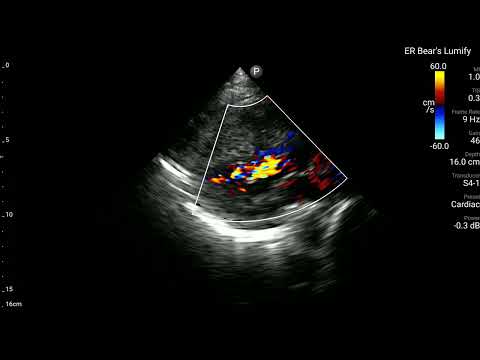

當時,在Bedside也有幫病患做echo。

可以清楚看到RV整團mass lesion,在PLAX打開color flow,在RV也沒有明顯flow。在PSAX view可清楚看到RV dilate with D-sign。A4C view更是清楚看到RV塞滿東西。不管是tumor還是thrombus,基本上已經造成RV strain(RV明顯dilate)。進而看到ECG上面的變化。